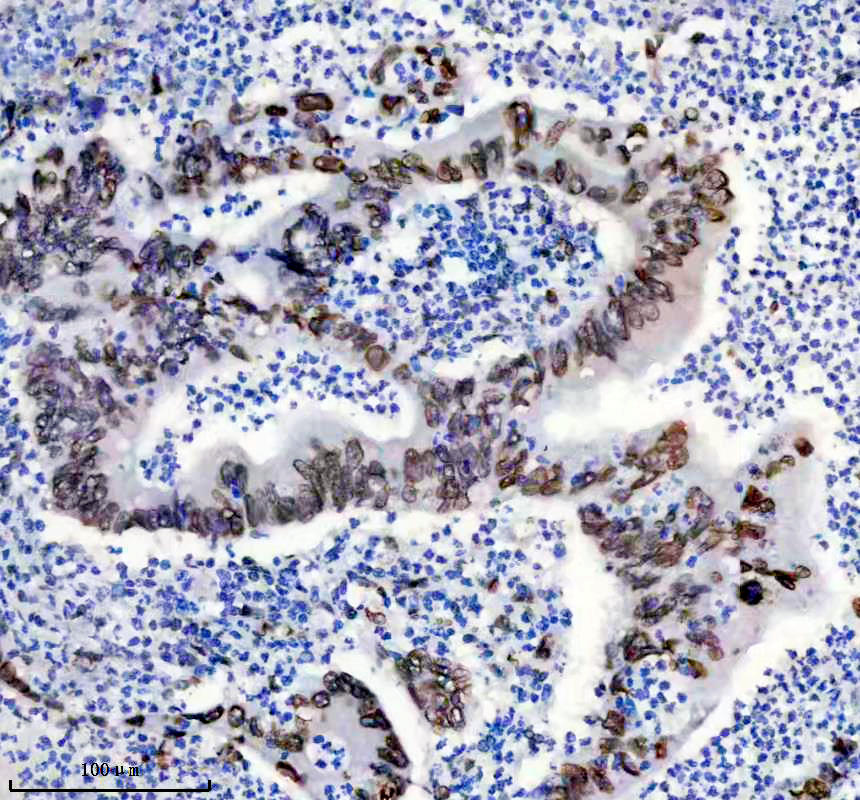

IHC analysis of Lamin A/C using anti-Lamin A/C antibody (BM4105).

Lamin A/C was detected in a paraffin-embedded section of human lung cancer tissue. The tissue section was incubated with rabbit anti-Lamin A/C Antibody (BM4105) at a dilution of 1:200 and developed using HRP Conjugated Rabbit IgG Super Vision Assay Kit (Catalog # SV0002) with DAB (Catalog # AR1027) as the chromogen.